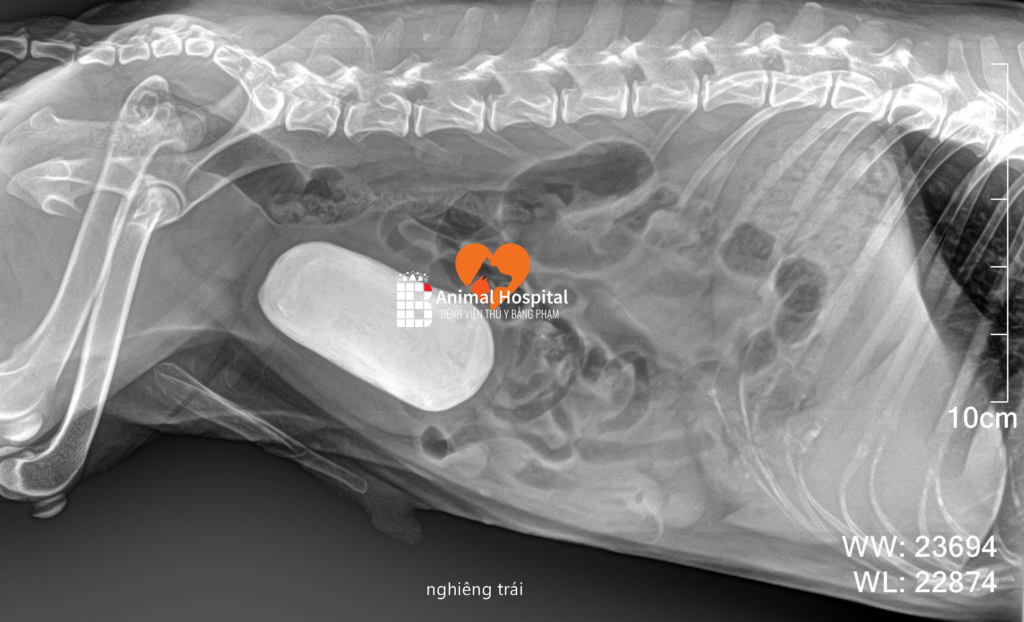

Ngay trên tấm phim X-quang đầu tiên, hình ảnh sỏi bàng quang ở chó đã lộ diện rõ nét với một khối cản quang hình bầu dục khổng lồ. Khối sỏi này lớn đến mức lấp đầy trọn vẹn thể tích của bàng quang, không còn không gian chứa nước tiểu.

sỏi bàng quang ở chó